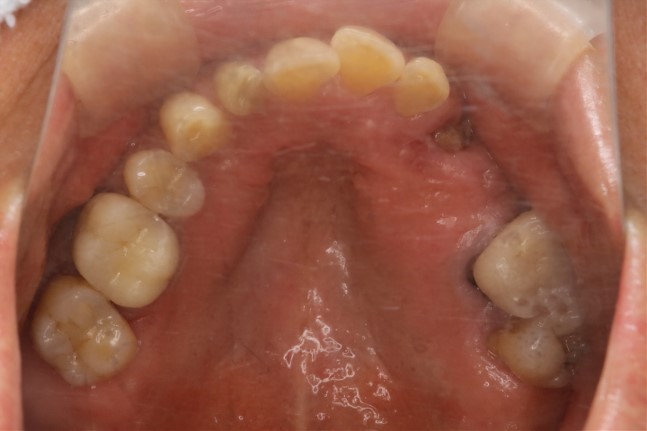

症例